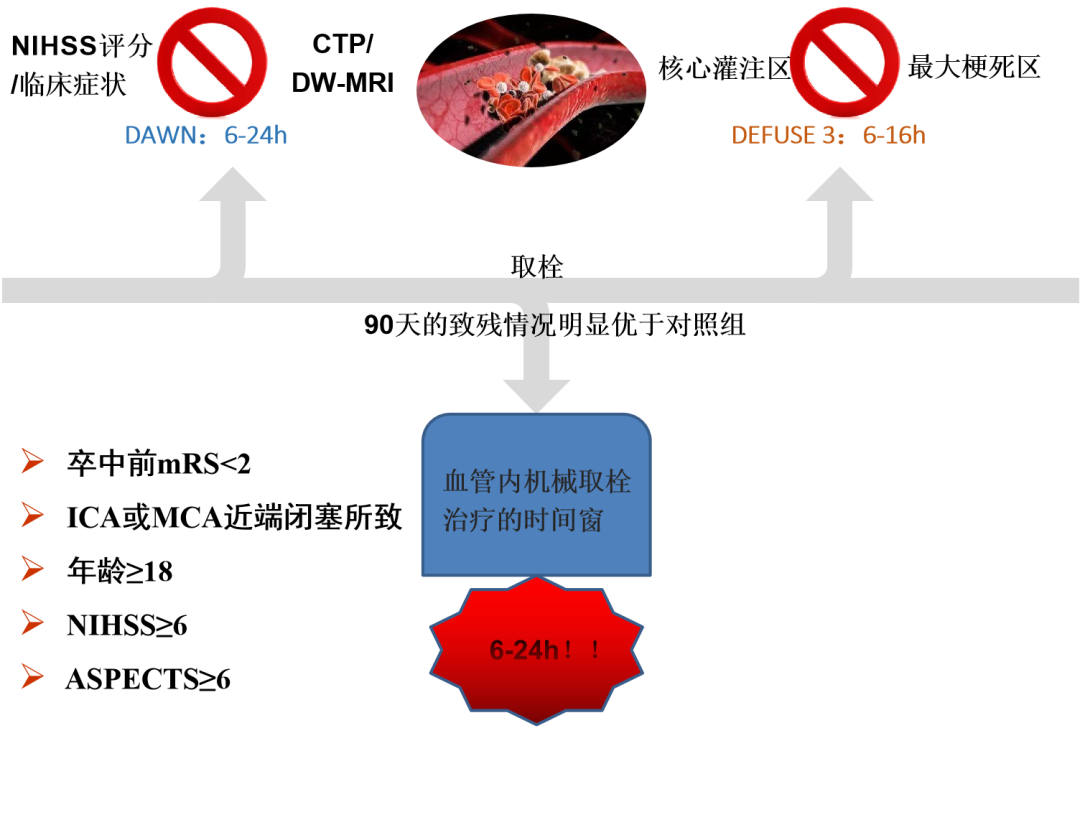

2018年1月24日,美国心脏协会/美国卒中协会(AHA/ASA)发布的《2018急性缺血性卒中患者早期管理指南》为临床医生处理成年急性缺血性卒中提供了一个最新最全面的建议。

大动脉闭塞性卒中采用以机械取栓为主的动脉内多模式治疗方法较传统的静脉溶栓能显著提高血管再通率,明显改善远期预后,且并不增加颅内出血率及病死率。

DAWN Trial

•ICA或MCA近端闭塞所致卒中

•年龄≥18

•卒中前mRS<2

•CT所见梗死区不超过MCA灌注区的1/3

•股动脉穿刺能在发病6-24小时内实施

•临床和影像间存在不匹配

结 果

•90天卒中相关死亡组间差别无统计学意义

•症状性颅内出血组间差别无统计学意义

DEFUSE 3(eligibility)

•卒中前mRS<2

•ICA或MCA近端闭塞所致卒中

•年龄:18-90

•NIHSS≥6

•股动脉穿刺能在发病6-16小时内实施

•影像检查存在梗死-灌注不匹配

核心梗死-灌注不匹配

•核心缺血区<70ml

•低灌注区:坏死区>1.8

•不匹配区域>15ml

•基于CTP或MRI成像或RAPID软件计算

总 结

2015年以来连续发表的6项RCT研究以及DAWN、DEFUSE 3研究证实,对伴有大血管闭塞的急性缺血性卒中患者行血管内介入治疗可显著改善患者90天临床预后。

《2018急性缺血性卒中患者早期管理指南》以最高等级的证据推荐了6~16小时的取栓治疗,以B-R级别的证据推荐了6~24小时的取栓治疗。